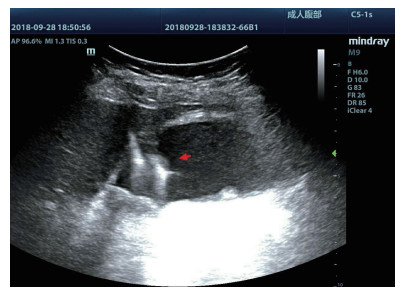

均采用塞丁格(Seldinger)技术置入引流管(图 4):穿刺穿刺点的选择①左侧卧位,超声确定胆囊床方位,取腋前线肋间或肋缘下进针; ②经肝的路径长度应大于2.0 cm胆囊穿刺点为中上部距离胆囊颈约1 /3的位置; ③穿刺路径上尽量避开大血管及大胆管结构; ④结合术前经肘静脉超声造影情况,避开胆囊穿孔部位及周边黏连组织。操作过程:由超声介入治疗组专业医师单人操作,为获得更自由的穿刺角度以及在穿刺过程中根据患者呼吸活动随时对进针角度进行调整,本组操作均未使用超声探头引导架。操作步骤①常规碘伏皮肤消毒,2%利多卡因局部麻醉至肝脏被膜。操作医师一手持超声探头,清晰显示进针入路,一手持18 G PTC穿刺针经皮经肝由胆囊床穿刺进入胆囊,拔出针芯,可见胆汁自行流出或用20 mL注射器回抽见胆汁。②沿针鞘置入导丝,超声探查见导丝进入胆囊,拔出针鞘。③扩张器扩张针道。④根据抽出胆汁的混浊程度,沿导丝置入合适型号的引流管,确定引流管通畅后拔出导丝,拉紧猪尾导管的外置固定线,使导管弯曲头牢固卷曲,形成内固定,皮肤缝线外固定引流管,双重固定更加有利于引流管留置于可靠位置,有效避免脱管。术后再次皮肤消毒,覆盖无菌贴膜。接引流袋。⑤术中及术后半h均予心电监测,术后常规送胆汁细菌培养,密切观察患者症状体征改善情况。

| 图 4 胆囊置管过程,导丝进入胆囊腔内(箭头处) |

超声造影是利用超声造影剂微泡(本组应用的是声诺维超声造影剂微泡)在低机械指数声波照射下发生共振,产生线性及非线性谐波回声信号,形成造影增强图像的技术,是近年来新兴的超声技术,具有实时、可连续观察、无辐射、可重复性好、毒不良反应少等优势,为临床提供了全新的诊疗手段[14]。经肘静脉注入的标准配置超声造影剂是一种血池造影剂,可以反映组织的血流灌注情况同时亦被广泛应用于肝、脾、肾等实质性脏器破裂的诊断,其诊断的敏感性及特异性均明显优于二维超声,且与增强CT有较好的一致性[15-16]。本组病例术前经肘静脉注入标准配置造影剂后,胆囊壁均显影增强,胆囊穿孔及周边积液处表现为造影无充盈区,穿刺置管后再次静脉路超声造影,迅速发现术后出血部位且可敏感评估是否为活动性出血(经手术证实)。除1例因活动性出血中转腹腔镜手术外,其余32例置管成功后经引流管口注入稀释造影剂20 mL(1:200稀释),评价引流管位置、引流范围及是否出现胆汁外漏取得良好效果,所有引流导管均能够清晰显示引流导管置入路径、引流管形态及引流范围,引流管置入恰当者,头端位于胆囊内,全管显影清晰,造影剂弥散区域与胆囊大小吻合; 置管后胆汁漏出者,可见造影剂沿引流管周边渗出[17-18],本组中3例出现造影剂外渗,其中两例渗出范围局限于胆囊床附近,未渗出至游离腹腔,患者腹痛症状稍有加剧,经胆囊减压及对症处理后好转,其中1例见造影剂渗出至肝肾间隙,患者腹痛症状加剧明显,考虑置管位置不当,余行急诊腹腔镜手术治疗,术中证实为系膜胆囊,且可见引流管侧孔部分外露。笔者的经验是,术前选择静脉路超声造影有助于对胆囊情况的评估及穿刺点的选择,术中正确选择穿刺针的入路有利于提高穿刺引流的成功率。首先是胆囊穿刺部位的选择应选择在靠近胆囊颈侧,此处胆囊位置比较固定,受体位影响较小,且胆囊床结缔组织较为固定,有助于将漏出胆汁包裹局限,其次是进针方向与胆囊床尽可能保持垂直,减少进针位置的偏移,同时置管成功后应即刻尽量抽尽胆囊内的感染性胆汁,生理盐水冲洗后行经引流管稀释超声造影有助于判断置管位置、引流范围及是否出现胆汁漏出,减少不必要的并发症发生率。穿刺引流后可以根据患者的营养状况待窦道形成稳定后择期拔除引流导管。对全身情况改善适合手术治疗且有手术意愿者可以考虑择期胆囊切除术。